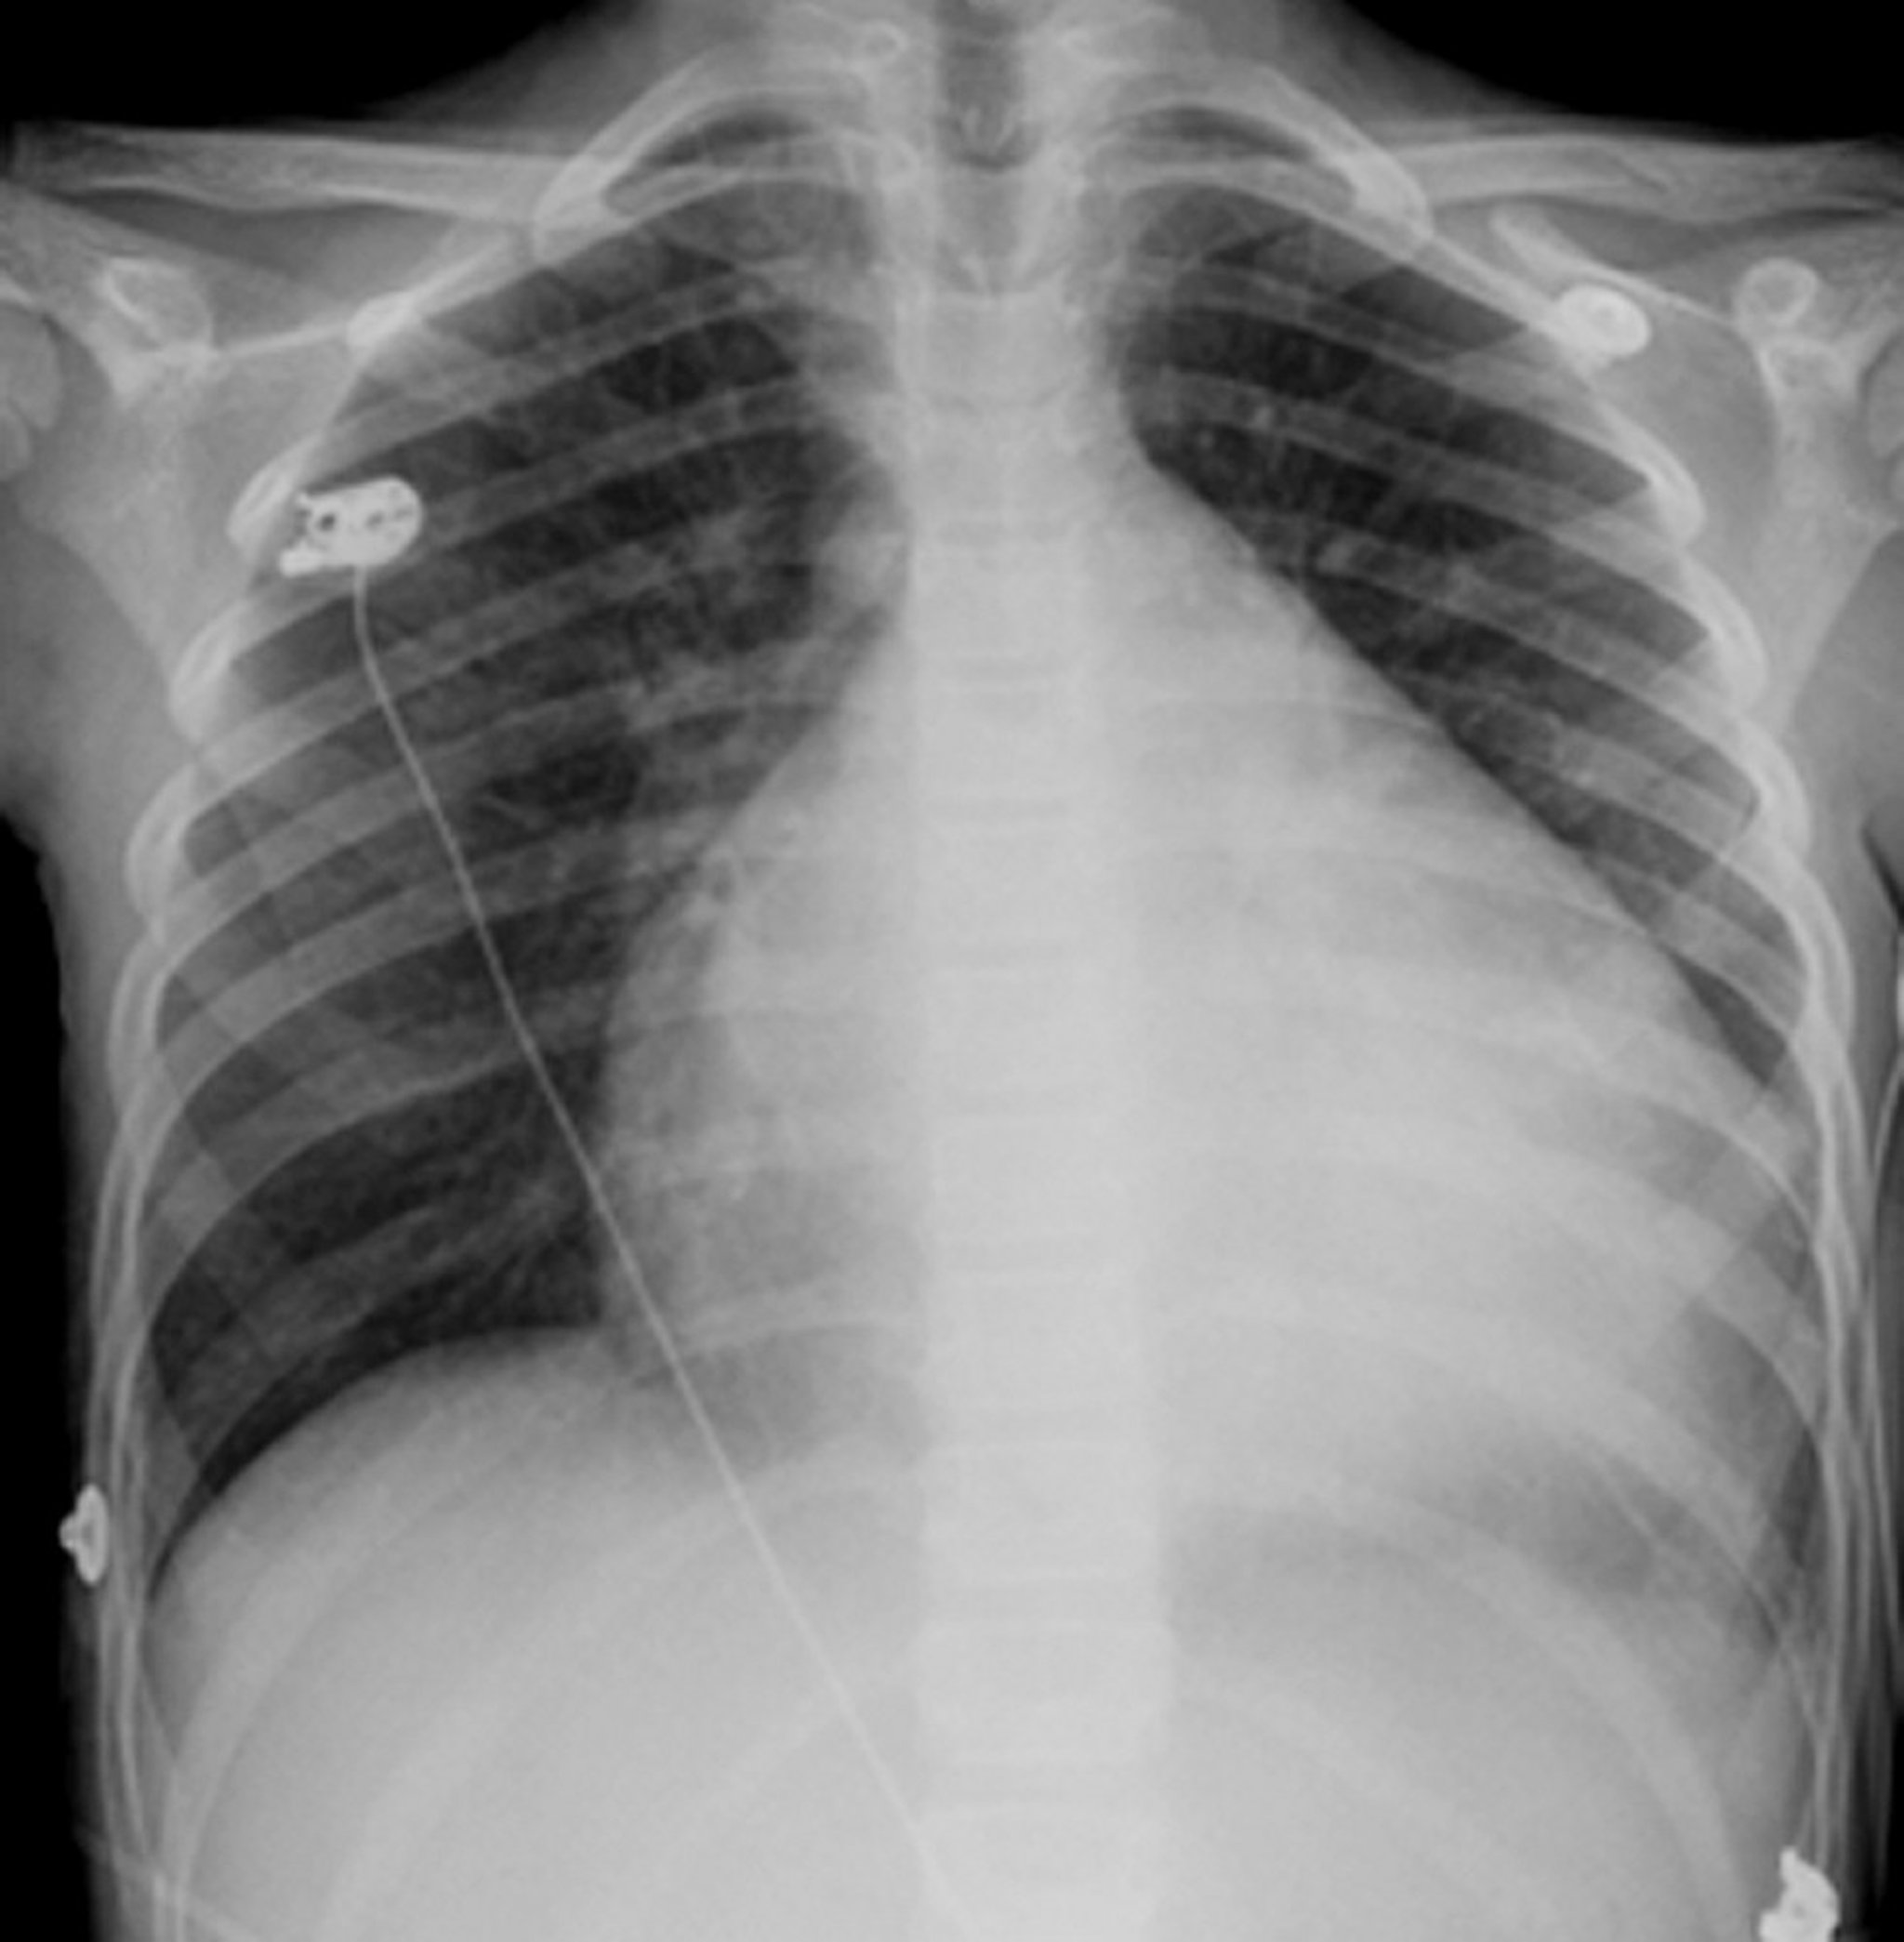

Enlarged Heart

The heart is the globular, white structure in the middle of the chest. Usually it occupies less than half the chest but, in this person who has an enlarged heart (cardiomyopathy), the heart is almost 3/4 the dimension of the chest.